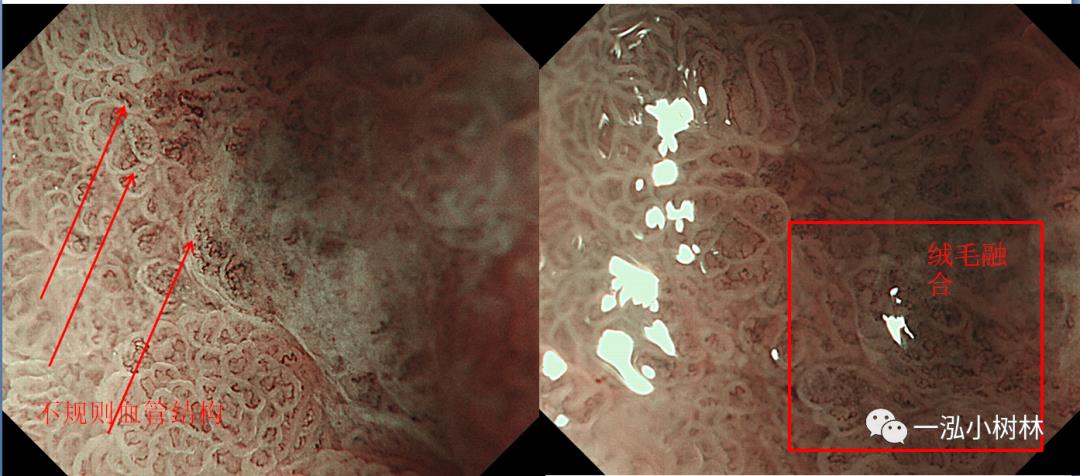

图7 ME-NBI:不规则绒毛结构+不规则微血管结构+绒毛融合

图7c ESD术后病理组织学:胃窦后壁高-中分化腺癌(Tub1>Tub2)